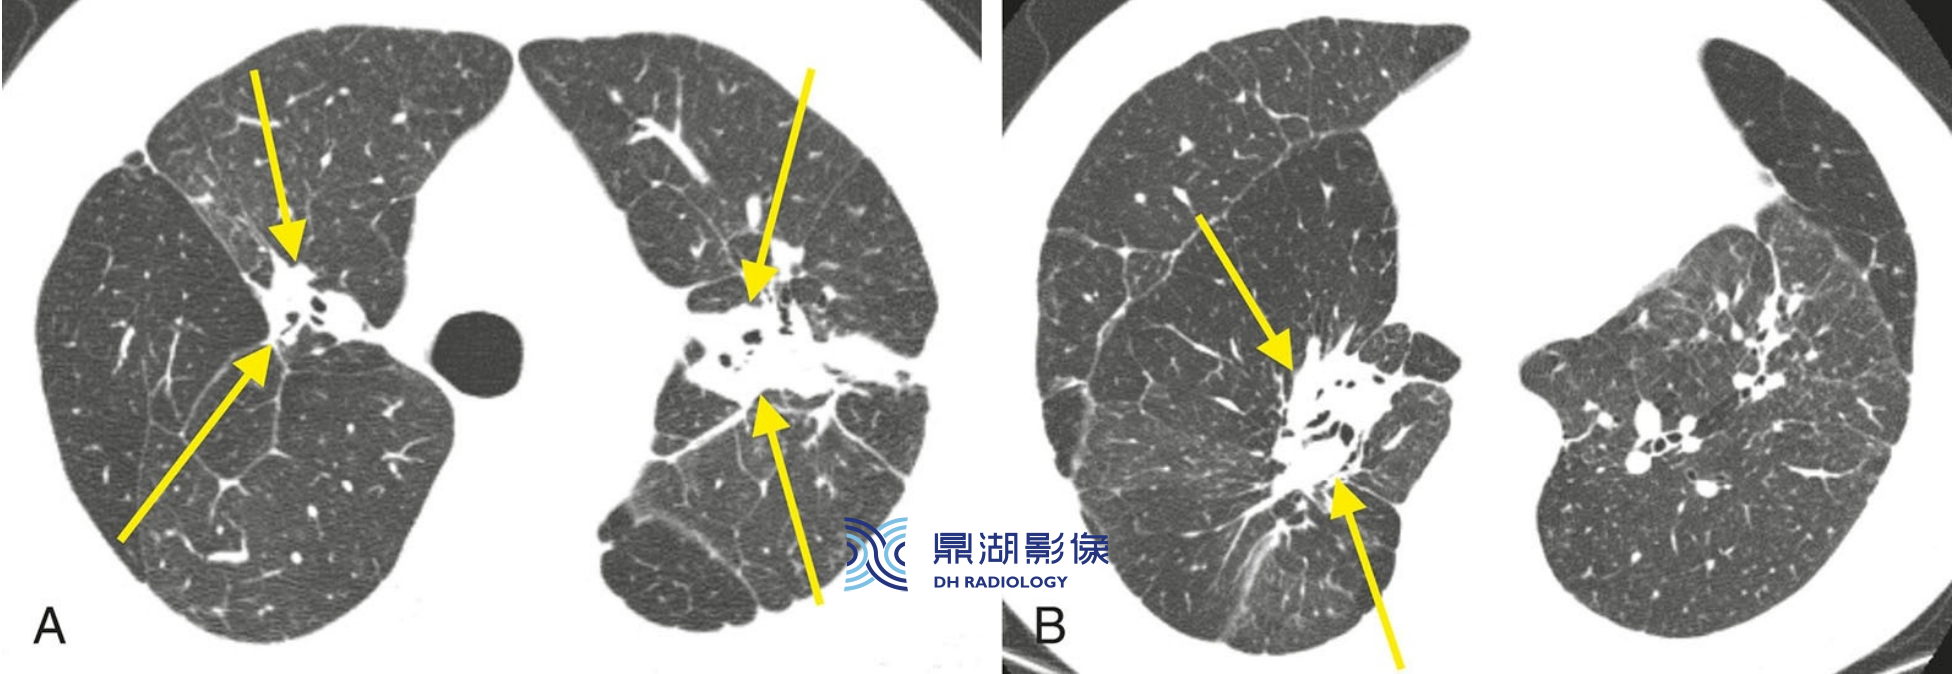

97d048a93c5f807a77b1817db175c7c1.png

2例结节病伴小叶间隔增厚。结节病很少以结节样小叶间隔增厚为主要异常表现。

A. 一例肺局限性受累的患者,左肺上叶可见串珠样的小叶间隔增厚(黄箭)。胸膜下也可见数个结节(红箭);

B.另一患者,串珠样的小叶间隔增厚(黄箭)主要见于右肺下叶,同样可见胸膜下结节(红箭)。